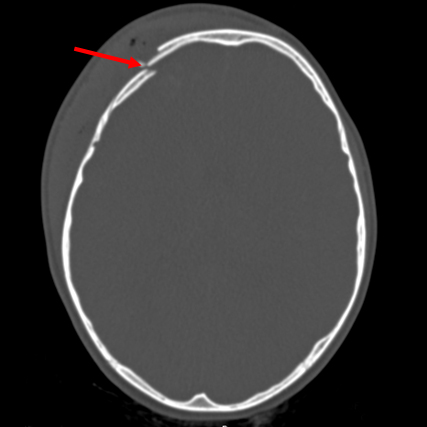

Linear parietal fracture without depression